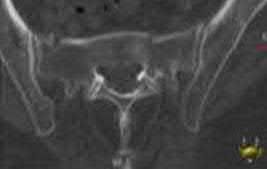

Question 23

A 35-year-old male sustains an APC-III pelvic ring injury following a high-speed motorcycle collision. After initial hemodynamic stabilization, the surgeon elects to perform an open reduction and internal fixation of a widened sacroiliac (SI) joint via an anterior approach. During dissection and plate placement over the sacral ala, which neurological structure is at greatest risk of iatrogenic injury?

Explanation

During the anterior approach to the sacroiliac joint, the L5 nerve root is at significant risk. It courses directly over the sacral ala, typically approximately 2 cm medial to the SI joint, before joining the sacral plexus. Retraction or misplaced drills/screws in this region can easily injure the L5 root, leading to foot drop and sensory deficits.